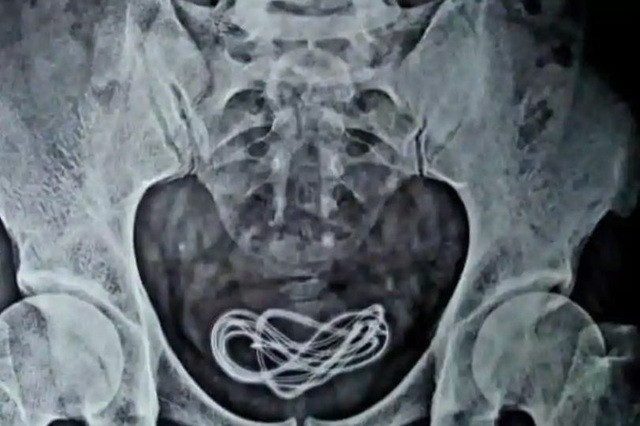

Bệnh nhân khai trót “ăn” dây sạc điện thoại, nhưng bác sĩ lại tìm thấy trong bàng quang ảnh 1Đoạn dây có thể được nhìn thấy rõ ràng trên ảnh chụp X-quang.

Kết quả phim cho thấy, một đoạn dây sạc điện thoại dài 70 cm bị mắc kẹt trong bàng quang chứ không phải dạ dày của bệnh nhân. Bác sĩ cho rằng bệnh nhân đã dùng dây cáp đâm xuyên qua phần dưới của mình.